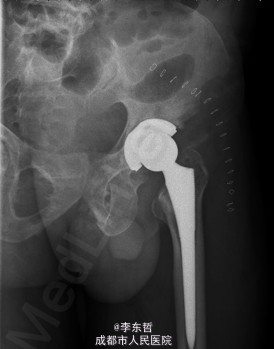

患者男,62岁,因“双髋疼痛4年,加重伴活动受限1年”入院。病员诉入院前4年无明显诱因出现双侧髋部疼痛,行走后疼痛加重,疼痛能忍受,双侧髋部无红肿,皮温不高,无畏寒、发热,休息后疼痛能自行缓解,无夜间疼痛,在当地医院行止痛药内服、理疗治疗,疼痛稍缓解。逐渐加重,1年前双侧髋部疼痛、跛行明显加重,左髋活动受限,行走困难,给予对症治疗症状无明显改善,遂到我科门诊就诊,X线片提示:双侧股骨头坏死,建议手术治疗,故于今日以“双侧侧股骨头坏死”收入我科进一步治疗。

查体:生命体征平稳,心肺腹未见异常;跛行,双左下肢较右下肢短缩1cm,左、右腹股沟中点深压痛,左、右髋叩击痛,左髋屈20°,伸0°,外展10°,内收10°,右髋屈60°,伸0°,外展20°,内收20°。双髋内、外旋活动受限,诱发疼痛,左侧重。 辅助检查:x线片示双侧股骨头坏死、塌陷变形,左侧明显,左髋半脱位。

初步诊断:1、左侧股骨头坏死伴内收肌挛缩(Ficat IV期);2、右侧股骨头坏死(Ficat IV期);3、右膝骨关节炎伴外翻畸形;入院后积极完善术前检查及准备,择期行手术治疗。